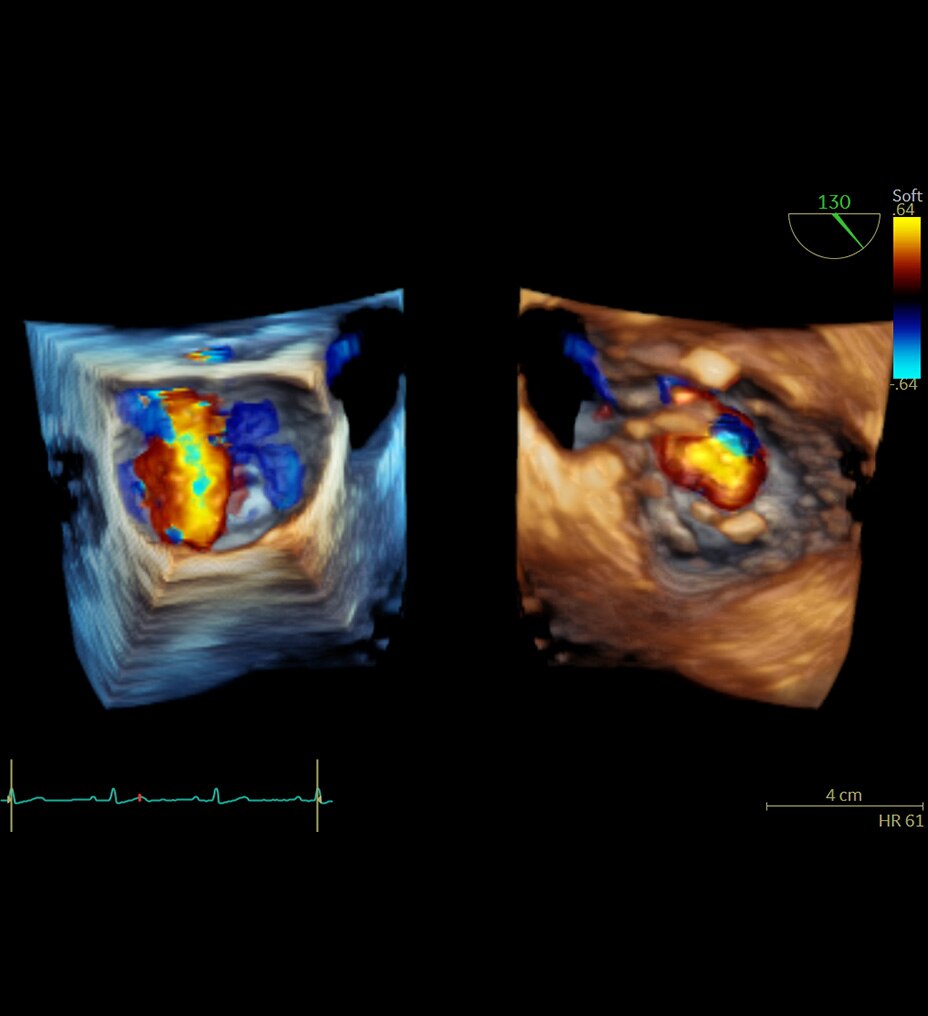

Structural heart:

Streamlined workflow for planning and augmented guidance with Valve Assist 23.

• -33% volume of contrast media4 and-33% X-ray dose in TAVI procedures5.

• Enhanced communication within the heart team with Allia x Vivid™ E95.